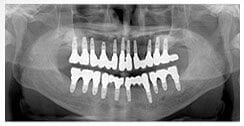

X 光片

術前X光片

術後X光片